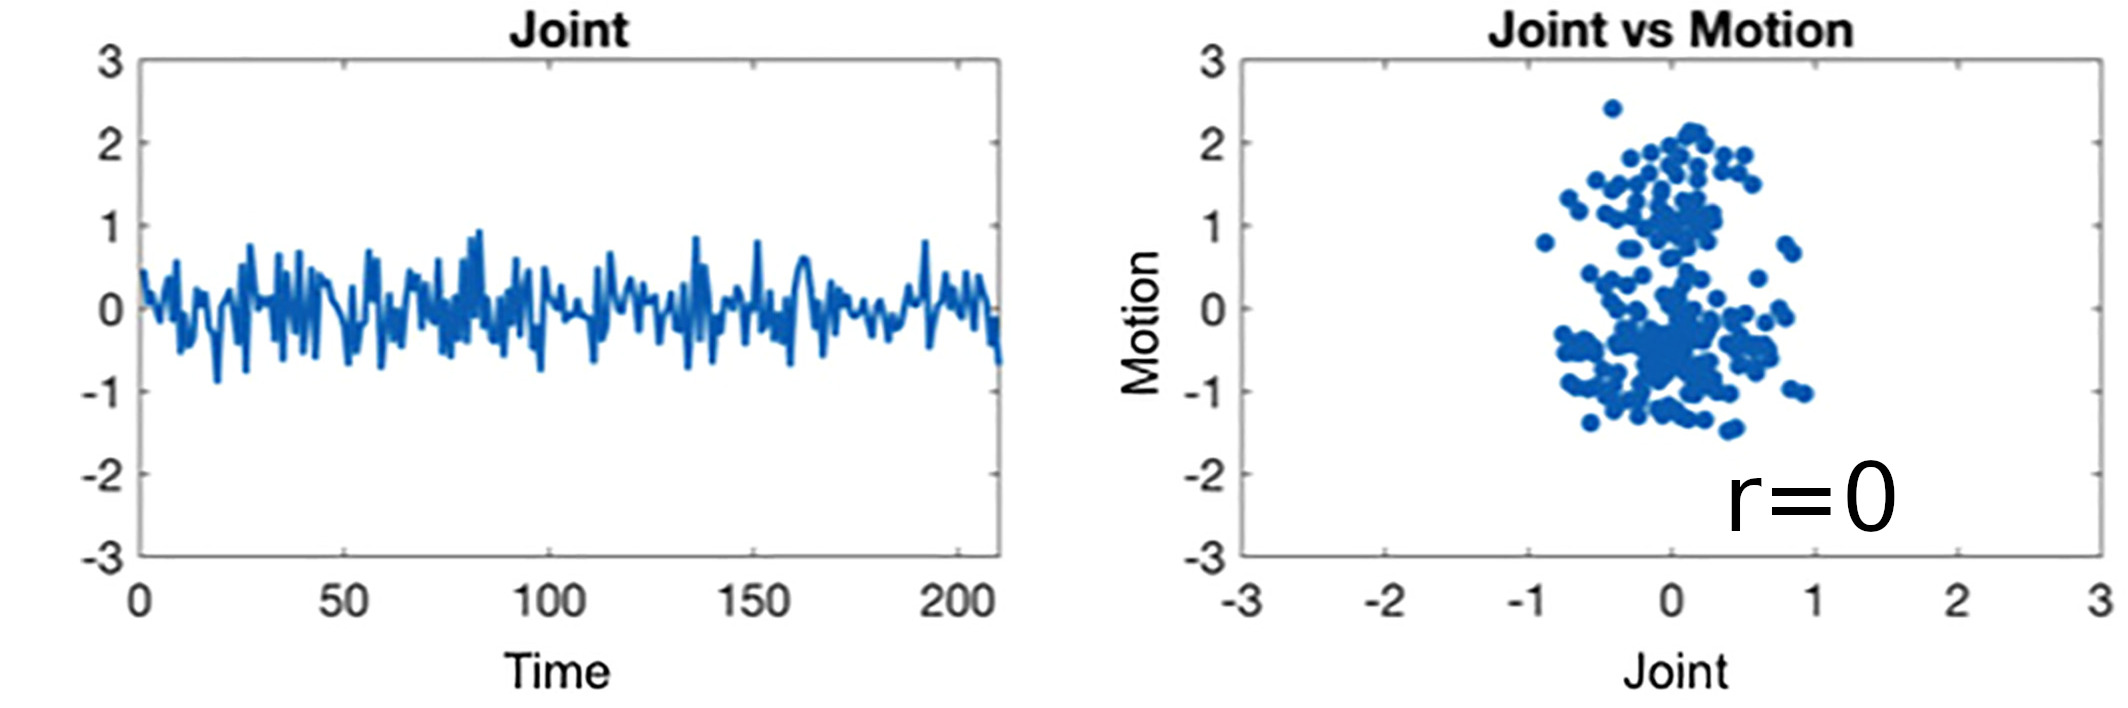

Sequential vs Simultaneous denoising

Performing denoising in sequential steps, rather than in parallel, might reintroduce removed artefacts

Lindquist et al. 2019 (Hum. Brain Mapp.)

Methods: CVR and lag maps

CVR and lag maps: L-GLM with each lagged regressor and nuisance regressors (12 motion parameters and low frequency trends), voxelwise selection of the lagged model with highest explained variance (R²), normalisation to MNI152 template (2.5 mm isotropic)

We compared four pipelines:

- L-GLM with motion parameters (see above, SimMot): $$ Y = P_{ET}CO_2{hrf}_{vx} + Mot + Poly + n $$

- Non-optimised CVR map (measurement delay only, Non Opt): $$ Y = P_{ET}CO_2{hrf}_{bulk} +n $$

- L-GLM without motion parameters (NoMot): $$ Y = P_{ET}CO_2{hrf}_{vx} + n $$

- L-GLM without motion parameters, motion regressed out before (SeqMot): $$ [Y \perp (Mot,Poly)] = P_{ET}CO_2{hrf}_{vx} + n $$

We compared four pipelines:

- L-GLM with motion parameters (see above, SimMot): $$ Y = P_{ET}CO_2{hrf}_{vx} + Mot + Poly + n $$

- Non-optimised CVR map (measurement delay only, Non Opt): $$ Y = P_{ET}CO_2{hrf}_{bulk} +n $$

- L-GLM without motion parameters (NoMot): $$ Y = P_{ET}CO_2{hrf}_{vx} + n $$

- L-GLM without motion parameters, motion regressed out before (SeqMot): $$ [Y \perp (Mot,Poly)] = P_{ET}CO_2{hrf}_{vx} + n $$

To improve CVR estimates, compute lagged-regression of signal of interest and noise simultaneously.

Take home message #2